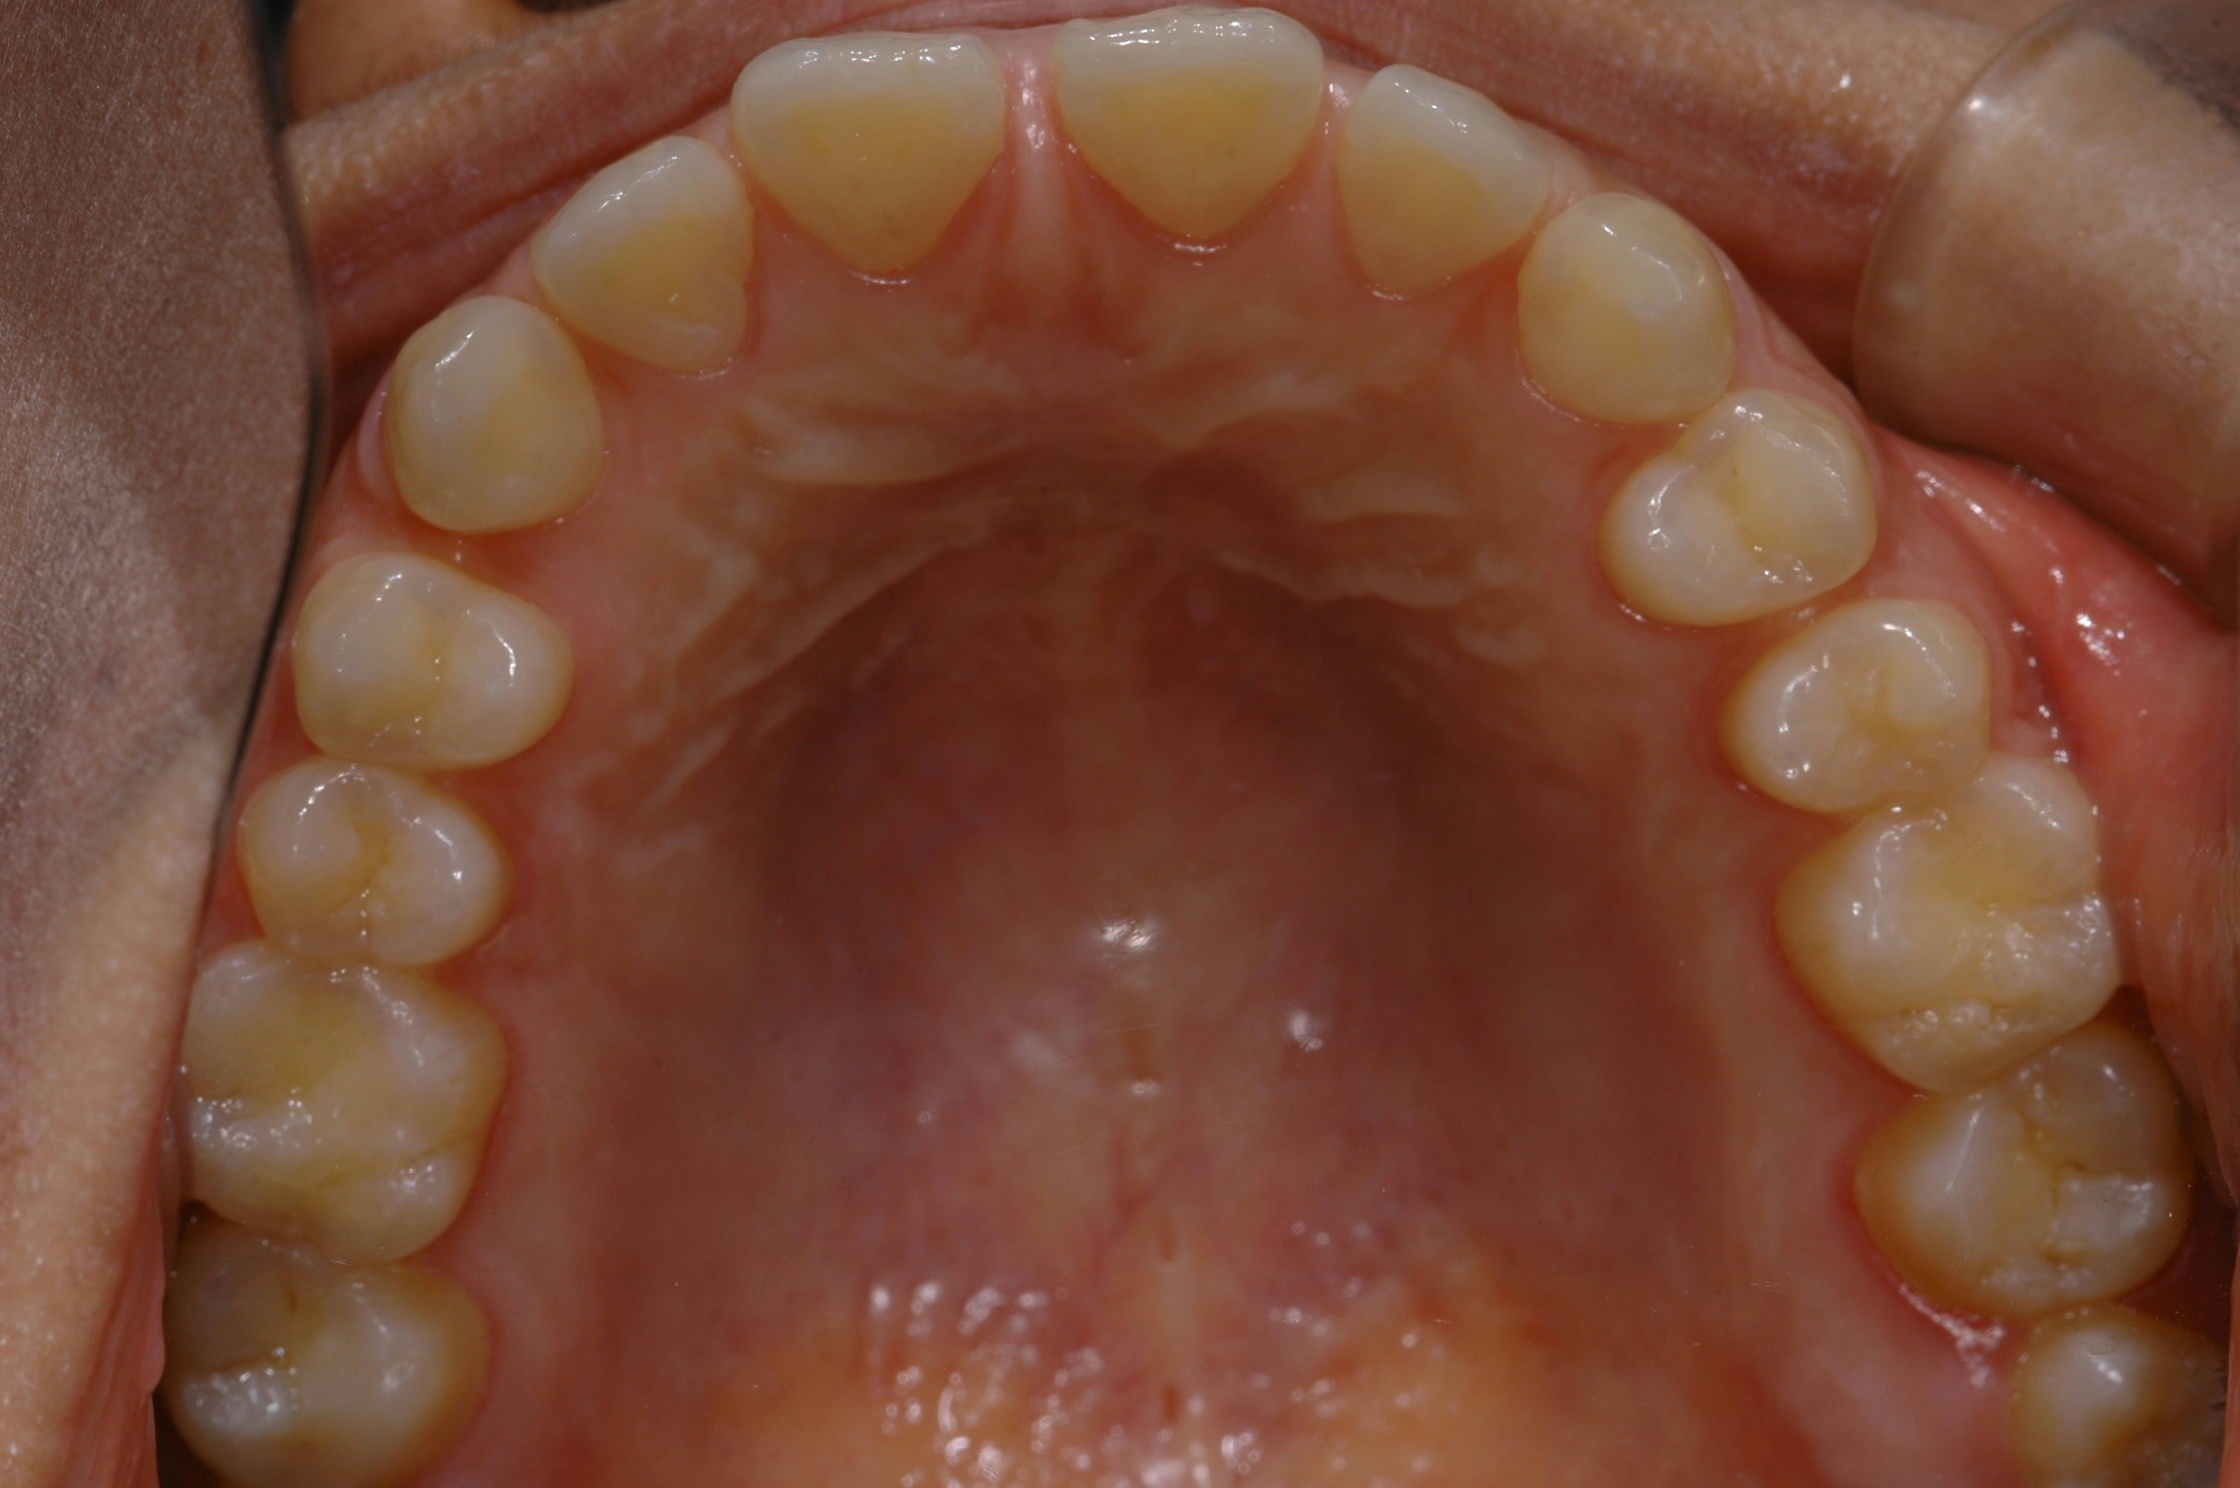

치료 전 사진입니다.